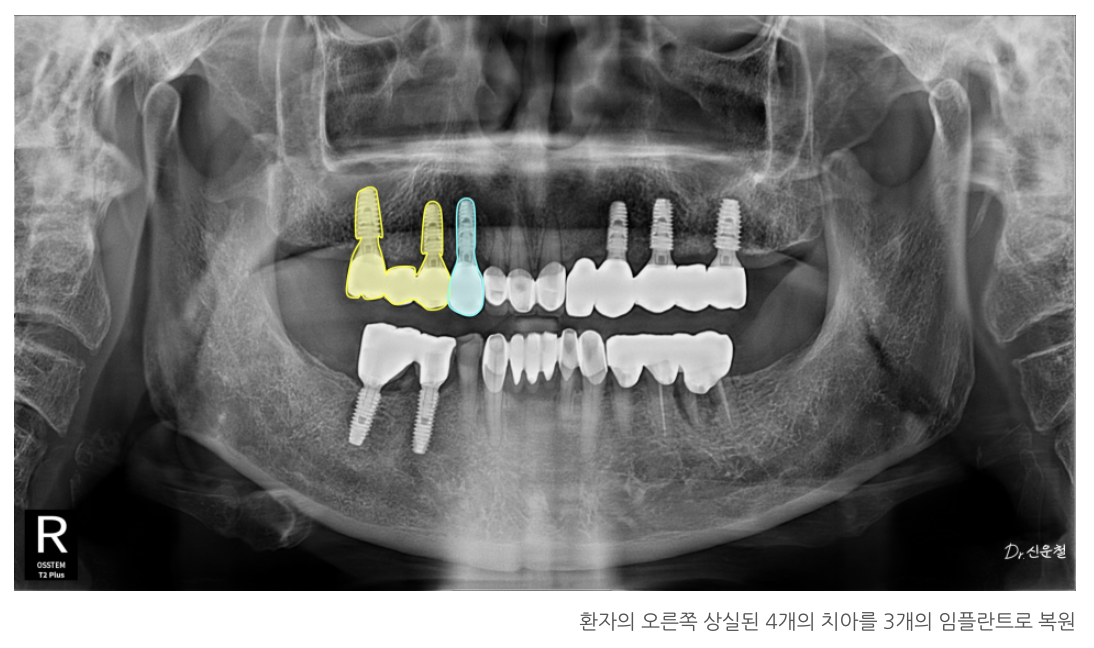

[오른쪽 치료 과정]

4개 상실 → 임플란트 3개로 복원

오른쪽은 치아가 4개 연속으로 빠져 있었습니다.

✔ 뒤쪽 힘이 안정적인 두 자리에만 임플란트를 식립

✔ 3개 치아 역할을 할 수 있도록 다리 구조로 제작

했습니다.

남은 앞쪽 1개는 단독 임플란트로 자연스럽게 회복했습니다.

5개 상실 → 안정된 3개로 복원

왼쪽은 앞쪽부터 뒤쪽까지 총 5개가 빠져 있었습니다.

한 줄 길게 만들면

양 끝에서 서로 잡아당기는 힘 때문에 오래 버티기 힘들기 때문에

오른쪽과 동일하게

✔ 튼튼한 두 곳에만 임플란트 식립

✔ 그 사이 치아는 자연스럽게 연결하여 3개 회복

✔ 앞니 2개가 빠져 있어도 ‘캔틸레버’로 한 개만 심었습니다

앞니는 어금니처럼 강한 힘을 받지 않기 때문에

임플란트 1개로도 2개 역할이 충분합니다.

특히 70대 환자분의 경우,

두 자리 중 한 곳은 뼈가 얇아 수술 부담이 컸기 때문에

더 안정적인 위치에만 임플란트를 심고

옆 치아는 자연스럽게 연결했습니다.

캔틸레버(Cantilever):

한쪽만 기둥이 있고 옆 치아는 떠 있는 형태의 연결 방식.